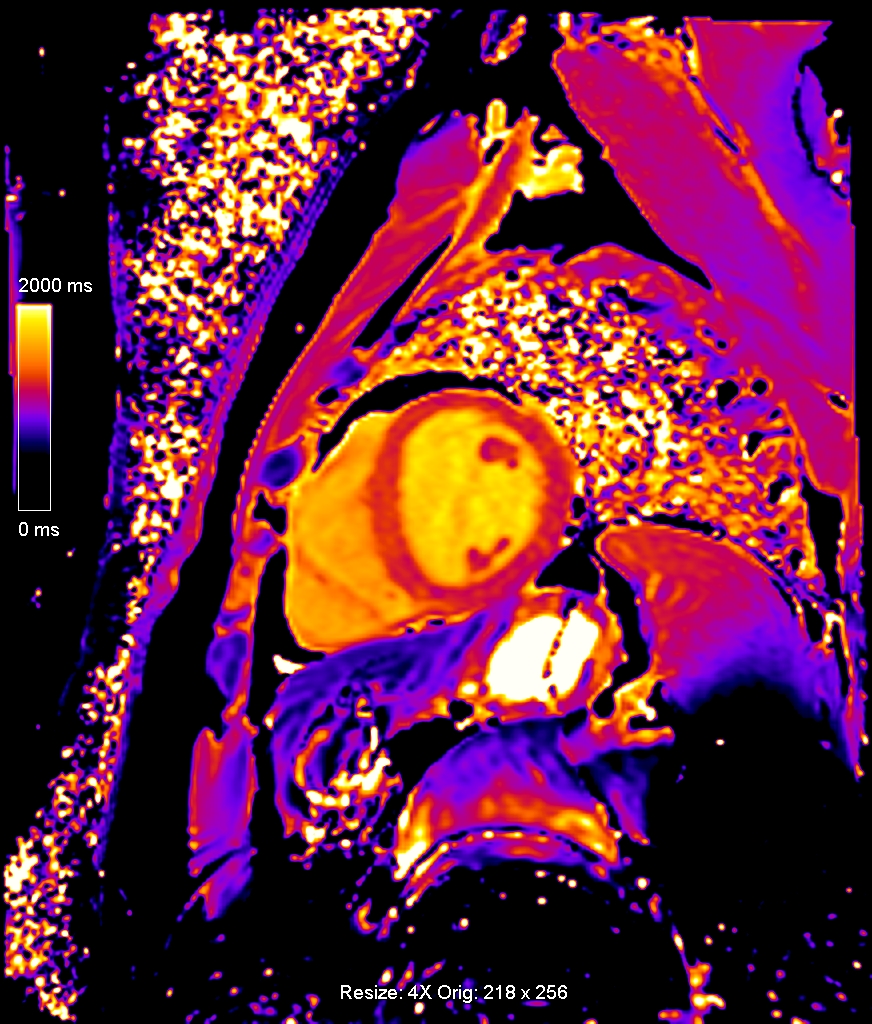

Τα βασικότερα πλεονεκτήματα της δυναμικής μαγνητικής τομογραφίας καρδιάς με αδενοσίνη (adenodine stress perfusion MRI) είναι η υψηλότερη ευαισθησία και ειδικότητα σε σχέση με τις υπόλοιπες διαγνωστικές μεθόδους δυναμικής απεικόνισης (σπινθηρογράφημα μυοκαρδίου, stress echo), η καταγραφή ακόμα και μικρών υπενδοκάρδιων ισχαιμικών περιοχών και μυοκαρδιακών ουλών, η καλύτερη διακριτική ικανότητα σε σχέση με το σπινθηρογράφημα του μυοκαρδίου και η ασφάλεια λόγω της απουσίας έκθεσης σε ιονίζουσα ακτινοβολία (εικόνες 1,2).

Εικόνα 1. Δυναμική μαγνητική τομογραφία καρδιάς με αδενοσίνη: